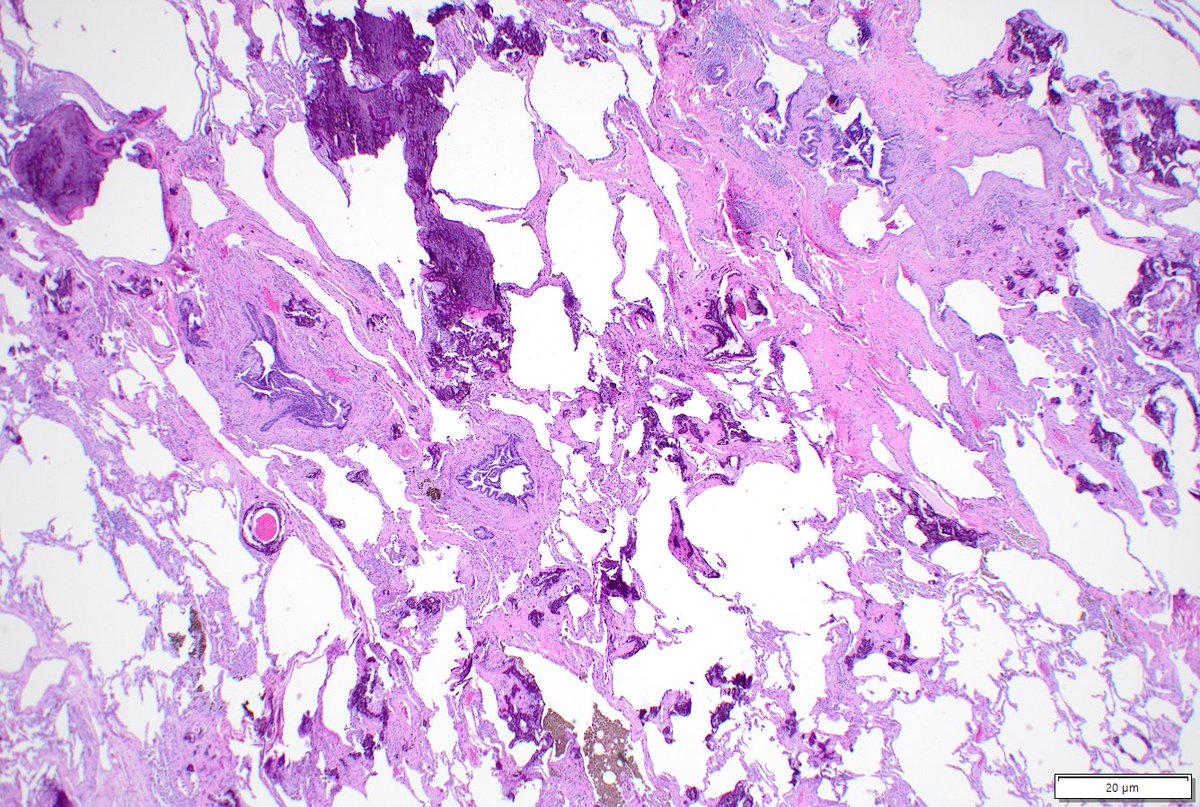

Incidental finding. Resection for met CA + CHF hx. Anything striking in alveolar septae imgs? Consider thoracic path training @MoffittNews "to contribute to the prevention and cure of cancer, focusing on groundbreaking research, expert patient care, and comprehensive education"

Diagnosing granulomatosis with polyangiitis on small biopsies (especially if not considering it) is very challenging. ANCA serologies, negative cultures, and pathologic suspicion were crucial in this case. Not everything is cancer at a cancer center. #lungpath #pathology #moffitt

Non-neoplastic lung pathology is a major part of my work at @MoffittNews. Consider training in thoracic pathology with us! We are still accepting fellows for 2026-2027. Today’s case: metastatic pulmonary calcification in a patient after massive transfusion #lung #pathology #MedEd